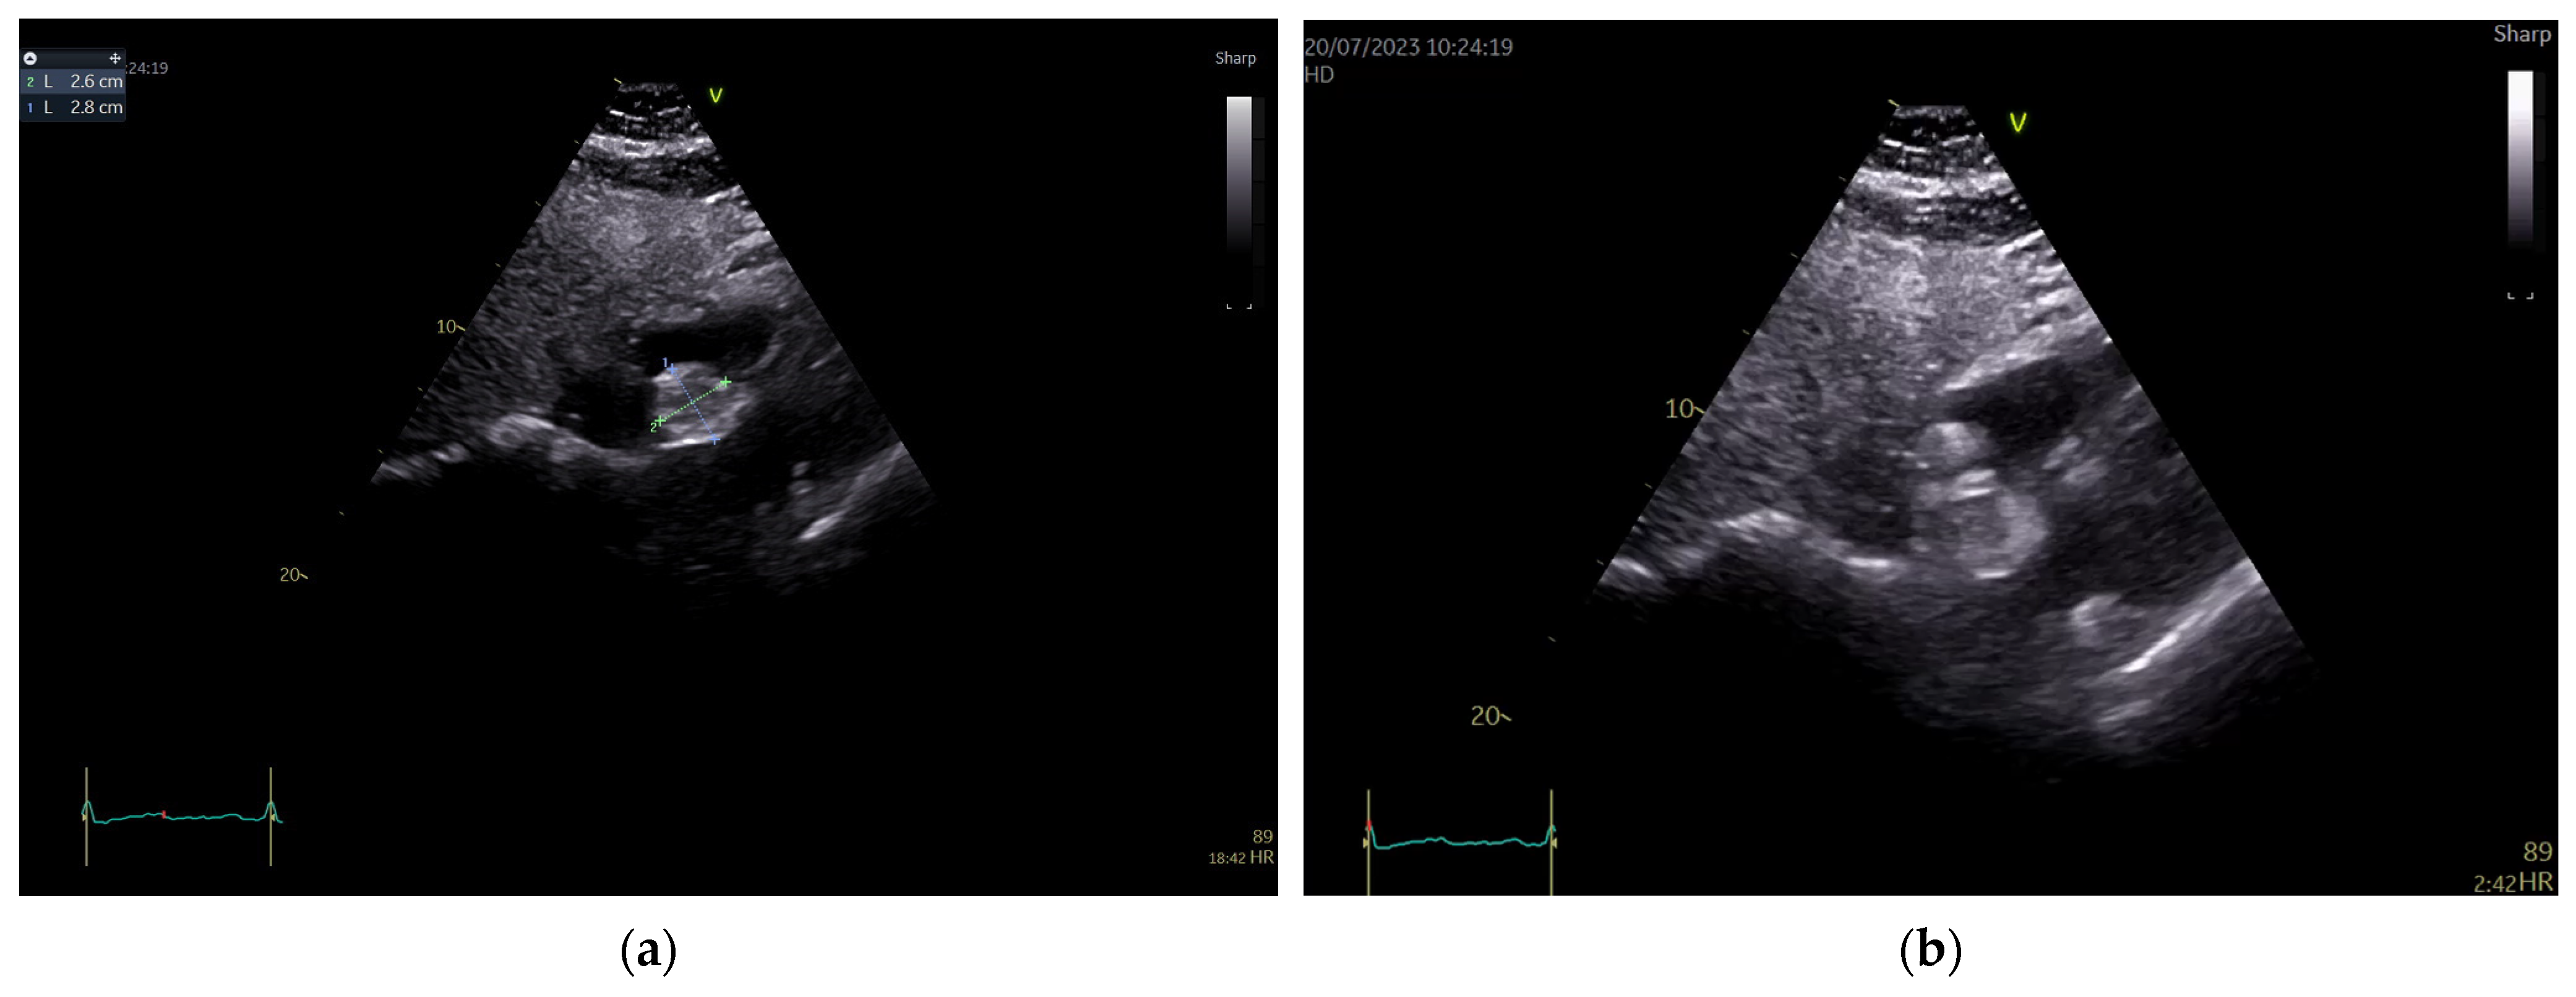

The patient’s standard blood tests as well as their resting electrocardiogram were within normal limits. Transthoracic echocardiography showed a normal-sized left ventricle with preserved ejection fraction (57% by tridimensional assessment) and a global longitudinal strain of −20.5%, as well as a normal-sized right ventricle with an ejection fraction within normal limits (50% by tridimensional assessment), thus demonstrating a non-significant cardiotoxic effect of chemotherapy until this moment. There was a mild degenerative mitral regurgitation associated with a mild functional tricuspid regurgitation, without any other valvular problems. In the apical four chamber and subcostal views though, a round-oval-shaped mass was identified in the right atrium apparently attached to the atrioventricular pole of the interatrial septum in a sessile manner. Pericardiac fat seemed well represented. The mass looked iso-hyperechogenic, slightly inhomogeneous, mobile with the IAS, and measured 28/26 mm. At first glance, it had an appearance similar to a myxoma. There was also a thickening of the RA wall detected (artefact? impregnation?) (Figure 1).

Figure 1.

Transthoracic echocardiography, subcostal views. A round-oval, apparently homogenous mass attached to the IAS is visualized bulging in the RA. (a) Measurement of the mass revealed diameters of 26/28 mm. (b) There is no clear delineation of the RA-free walls and an infiltration at this level cannot be excluded.